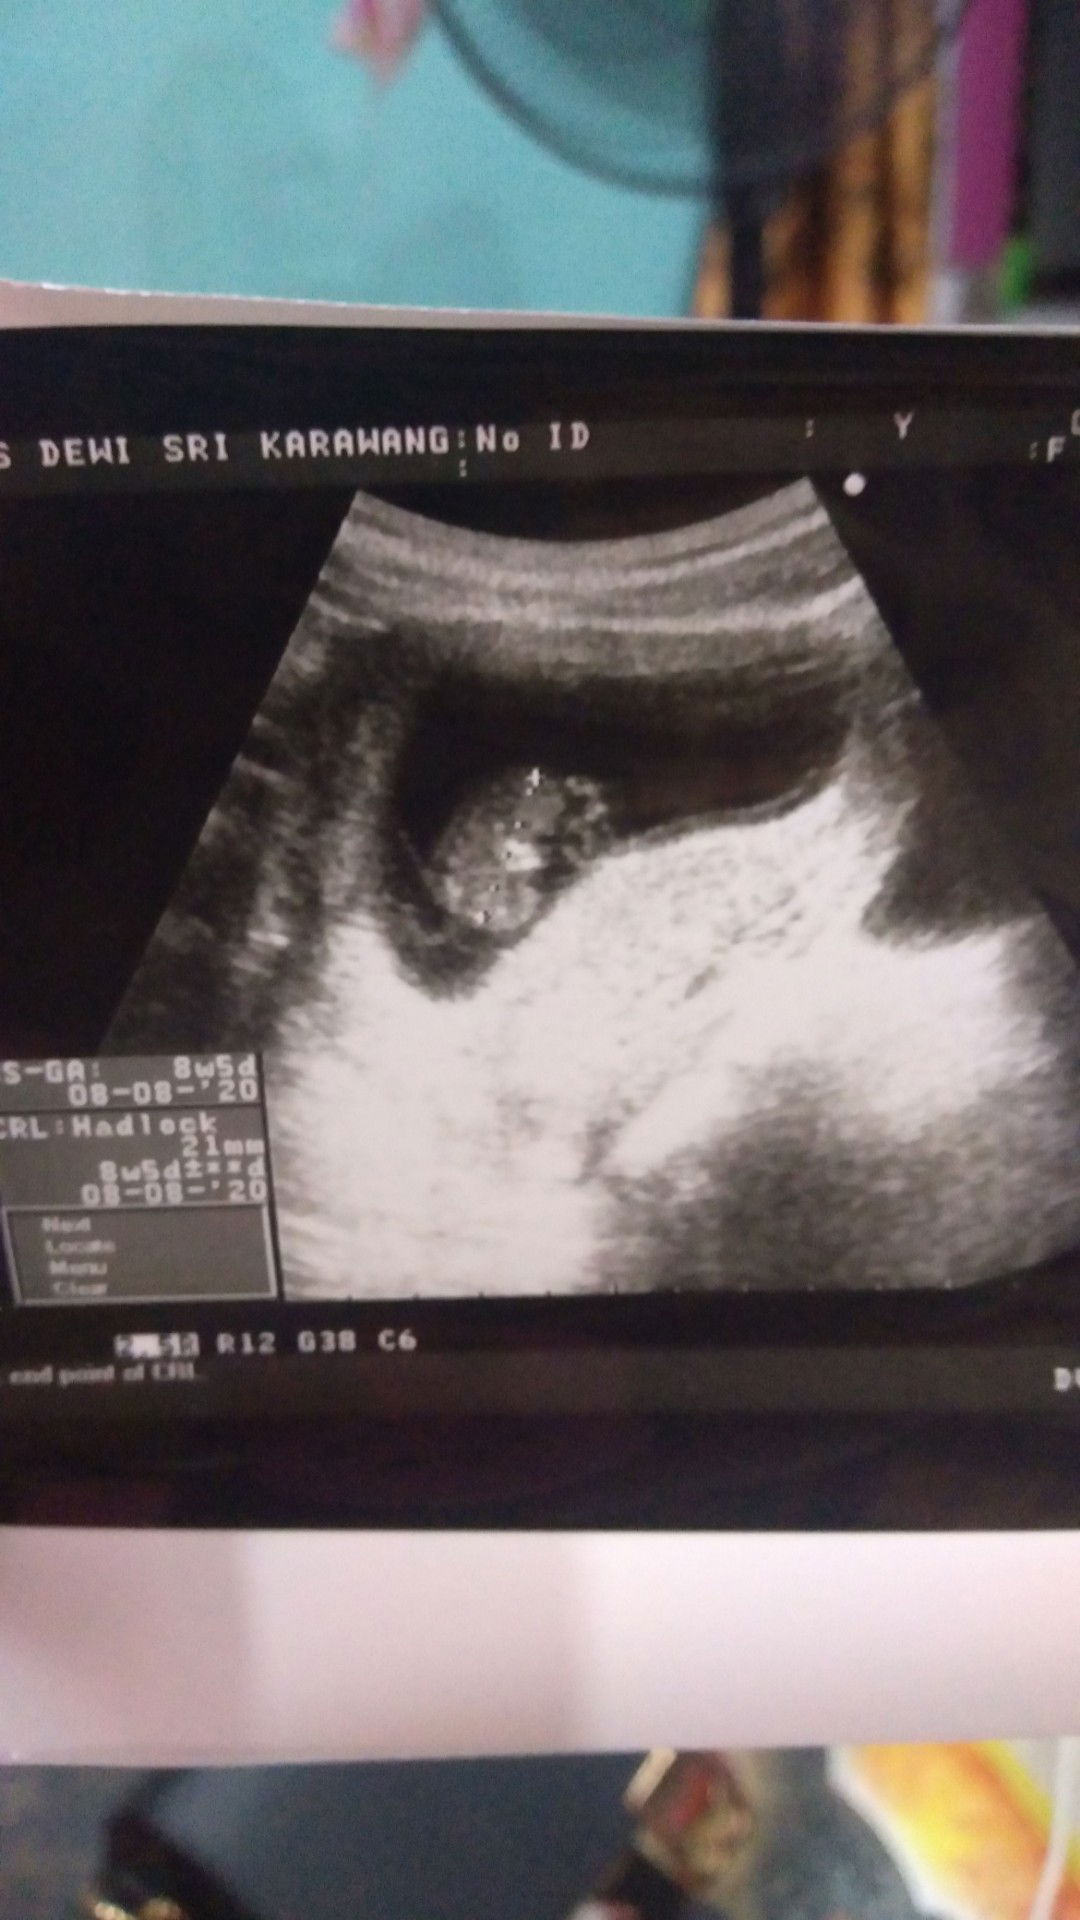

Usia kehamilan dilihat dari hpht atau dari USG

Tgl 13 Desember 2020 aku USG Karena liat hasil tespek garis 2 samar ternyata benar saya hamil 4 Minggu 6 hari. Dan dokter nyuruh aku balik lagi sebulan kemudian, pan saya balik lagi sebulan kemudian pas tgl 13 Januari 2021 ternyata usia kehamilan ku sudah memasuki 11 Minggu 5 hari. Jadi mana yg lebih akurat Bun, sesuai hpht apa sesuai hasil USG? #seriusnanya #bantusharing